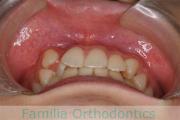

前歯の関係など

正面

- ≫治療後

-